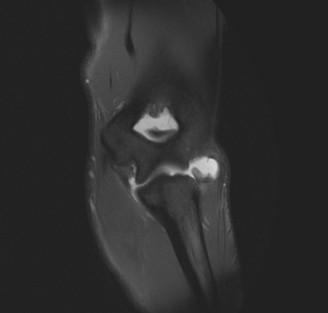

The patient undergoes resection arthroplasty with antibiotic cement spacer and a 6-week course of IV antibiotics. He returns to clinic 4 months later with improved pain, CRP <3, however, on examination he has a positive belly press sign and increased external rotation compared with the contralateral shoulder. Imaging is shown in Figure 2–57.

Figure 2–57

The correct answer is (D). The patient has completed his course of antibiotics and his spacer and is now an appropriate candidate for explanation of the cement spacer with revision shoulder arthroplasty, therefore Choices A and C are incorrect. The patient’s clinical examination findings point to rotator cuff tear (specifically subscapularis) which has occurred in the interval between his obtaining his initial total shoulder arthroplasty and his current examination. Therefore, total shoulder arthroplasty (Choice B) is contraindicated, and the patient should have a reverse total shoulder arthroplasty. Objectives: Did you learn...? Recognize the clinical presentation of a patient with infection after total shoulder arthroplasty?